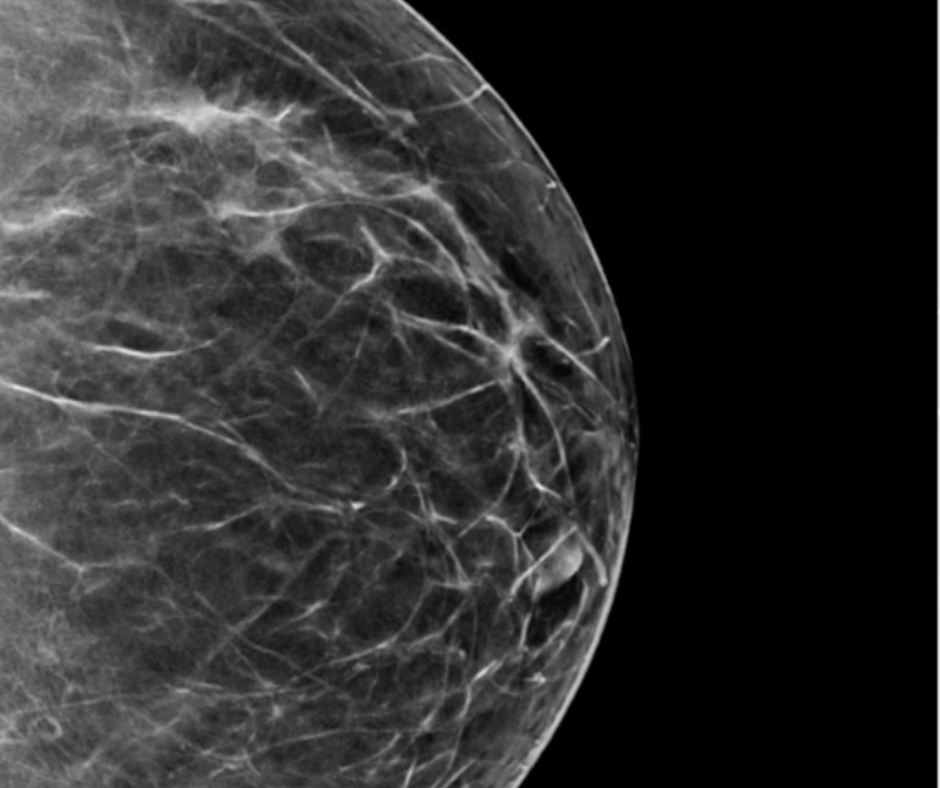

Researchers found that ChatGPT offered appropriate responses to 22 out of 25 patient-oriented questions on mammography screening, dense breasts, BI-RADS scoring and other topics related to breast cancer screening and prevention.